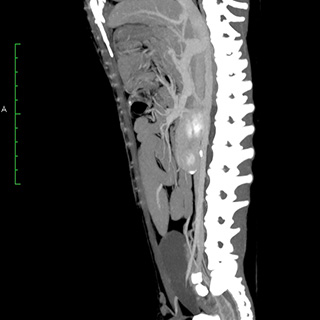

CT画像診断

CT検査により、通常の画像検査では検出しにくい病気の早期発見・診断につながる可能性が高まります。

CT画像の検査・読影のみも受け付けております。当院では画像診断アドバイザーとして柿崎竹彦先生(北里大学獣医学部獣医学科 獣医放射線学研究室講師)からアドバイスをいただいております。